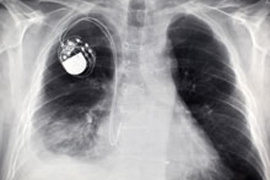

Швейцарские ученые произвели настоящий фурор на прошедшем в выходные ежегодном совещании Европейского общества кардиологов в Барселоне. Дело в том, что они представили новый кардиостимулятор, работающий без батареек. Суть в использовании принципа автоподзавода, как в наручных часах, пишет "NewsRU Israel".

Современные кардиостимуляторы эффективно регулируют ритм сердцебиения, но с ними есть проблемы. Основная - необходимость подзарядки. А чтобы поменять в устройстве батарею, необходимо провести полноценную операцию. Отказаться от батареек удалось инженеру Адриану Зурбахену из Бернского университета.

За основу он взял часовой механизм с автоматическим заводом, разработанный для карманных часов швейцарской марки Abraham-Louis Perrelet в 1777 году. Подобно тому, как наручные часы заряжаются при перемещении по запястью благодаря заводу пружины, механизм в кардиостимуляторе генерирует электрический ток, используя движения сердечной мышцы.

Но тогда стимулятор нужно имплантировать прямо в сердце. Подход уже опробовали на свиньях. Стимулятор давал устойчивый ритм сердцебиения в 130 ударов в минуту. Когда кардиостимулятор испытают на людях, пока не сообщается.